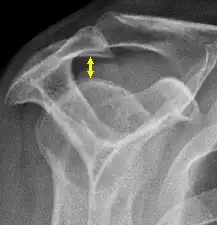

L'espace gléno-huméral normal est de 4 à 5 mm[3].

L'espace sous-acromial normal sur les radiographies de l'épaule est de 9 à 10 millimètres ; cet espace est significativement plus important chez les hommes, avec une légère diminution avec l'âge[4]. A l'âge moyen, un espace sous-acromial inférieur à 6 mm est pathologique et peut indiquer une rupture du tendon du muscle supra-épineux[4].